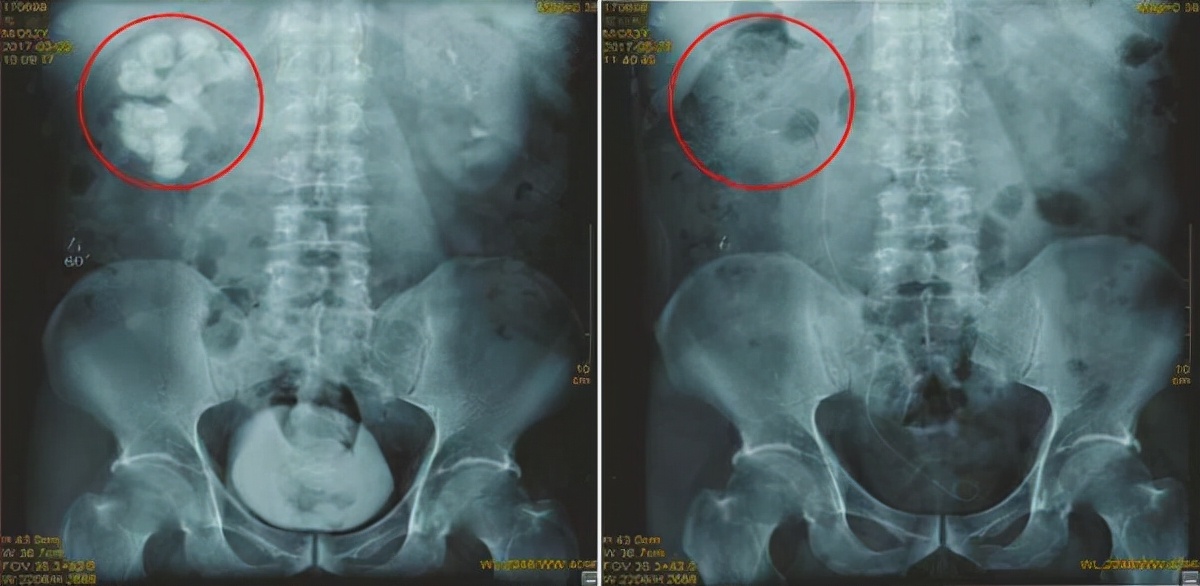

后来,这个患者在朋友的介绍下来到了我院,经过再次专业检查,我们发现这个患者右肾已经被结石塞得连多余的空隙都没有,长度达10cm,右肾功能也只剩下2成左右,真是让人感到惋惜!

幸运的是,邹先生在接受了5次手术,包括4次经皮肾镜碎石取石术、1次输尿管软镜碎石取石术后,最终才将右肾结石彻底清除干净。

图:手术前后对比图